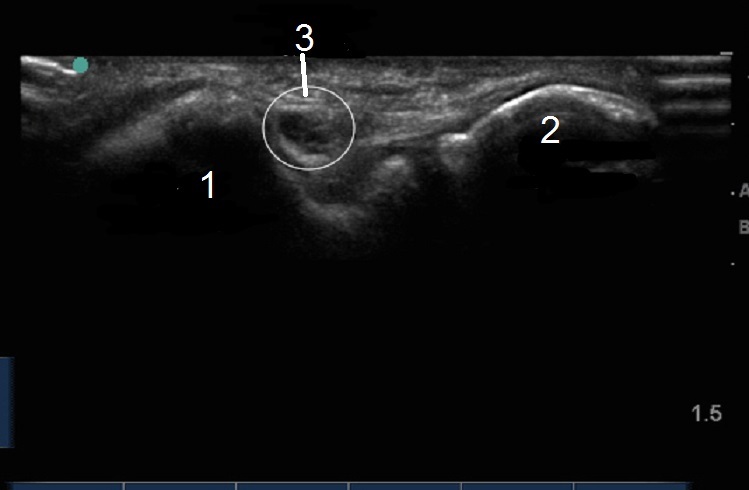

Elbow Cubital Tunnel Transverse 2 Image

Medial Epicondyle

Olecranon Process

Ulnar Nerve